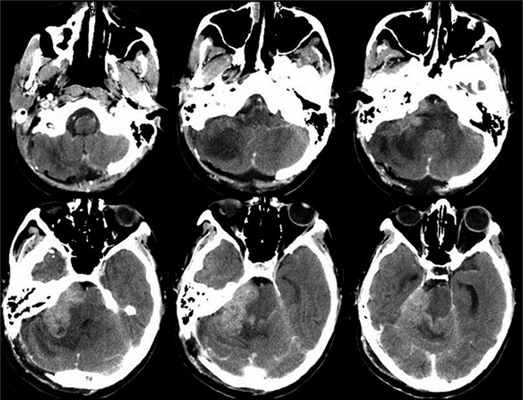

В результате выполненной 02.12.15 МРТ головного мозга с контрастным усилением, показавшей наличие интраканальной опухоли, распространяющейся в сторону мостомозжечковой цистерны, заподозрена невринома слухового нерва. Было принято решение проводить динамическое наблюдение. Однако 14.12.15 остро развилась слабость лицевой мускулатуры, стала нарастать интенсивность головокружений. Внепланово была выполнена контрольная МРТ головного мозга 13.01.16, где отмечалось увеличение экстраканальной части опухоли почти в 2 раза. В течение подготовки к хирургическому лечению отмечалось значительное ухудшение состояния: нарастание статодинамических нарушений, увеличение выраженности симптоматики со стороны правого мостомозжечкового угла, появление бульбарных нарушений, выраженных общемозговых симптомов. По МРТ головного мозга от 22.02.16 отмечалась прогрессия экстраканальной части опухоли до 3 см. На фоне терапии глюкокортикоидами, обезболивающими и противорвотными препаратами состояние пациентки стабилизировалось.

Учитывая темп развития симптомов, был заподозрен злокачественный характер опухоли. В день поступления (02.03.16) пациентке выполнена МРТ головного мозга и спинного мозга с контрастным усилением. Была выявлена диссеминация процесса с появлением опухоли в левом внутреннем слуховом проходе, множественных очагов патологического накопления контрастного вещества оболочек спинного мозга. Динамика распространения первичного очага и метастазирование представлены на рис. 1 и 2.

Рис. 3. Рис 3. КТ головного мозга, выполненная на 6-е сутки после операции. Признаки быстрого продолженного роста опухоли.